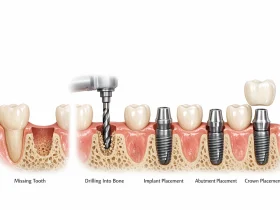

اوردنچر نوعی پروتز متحرک دندانی است که بر روی ریشه دندانهای باقیمانده یا ایمپلنتهای دندانی قرار میگیرد. در واقع این نوع پروتز علاوه بر لثه، از ساختارهای زیرین مانند ریشه دندان یا پایه ایمپلنت نیز حمایت دریافت میکند.

در این روش معمولاً چند ریشه دندان طبیعی یا چند پایه ایمپلنت در داخل استخوان فک حفظ میشوند و پروتز دندانی به کمک اتصالات مخصوص روی آنها قرار میگیرد. این اتصال باعث میشود دندان مصنوعی ثبات بیشتری در دهان داشته باشد و هنگام صحبت یا غذا خوردن کمتر حرکت کند.

از نظر ظاهری، اوردنچر شباهت زیادی به دندان مصنوعی کامل دارد؛ با این تفاوت که در بخش زیرین آن اتصالاتی وجود دارد که به ایمپلنت یا ریشه دندان متصل میشوند. این اتصال میتواند به صورت گوی و سوکت یا میلهای باشد که پروتز روی آن قفل میشود.